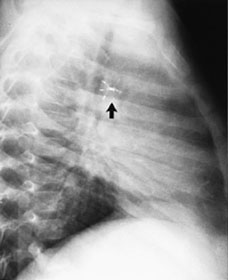

Rashkinds paraplymetode for ductuslukking er nøye beskrevet tidligere (1 – 3). I prinsippet er det en tre- eller firearmet dobbelt automatparaply kledd med hver sin duk av polyuretanskum. Implantasjonen skjer ad venøs vei via en 8 eller 11 french innføringsskjede. Den distale paraply havner i ductusinfundibulum og klemmes sammen til en kjegle. Den andre åpnes i pulmonalarterien (fig 1). Både før og etter at paraplyen er frigjort fra innføringssystemet utføres aortografi med injeksjon av kontrastmiddel i aortabuen.